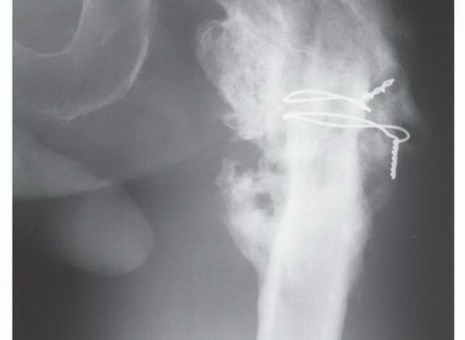

Using a sterile ruler and fluoroscopic guidance, the exact level of the femoral osteotomy is marked based on the preoperative MRI templating. The osteotomy is performed using an oscillating saw. The resected specimen is immediately handed off the field, and a marrow scraping from the remaining host bone is sent for stat frozen section analysis to definitively confirm a negative oncologic margin. If the margin is positive, further bone must be resected.

Once margins are cleared, the reconstruction phase begins. The distal femoral canal is sequentially reamed and broached to accept the definitive stem. If a cemented stem is chosen (typical for older patients or irradiated bone), a cement restrictor is placed, the canal is pulsatile lavaged, dried, and polymethylmethacrylate (PMMA) bone cement is injected in a retrograde fashion. The modular prosthesis is then assembled on the back table. The components—stem, intercalary segments, proximal body, and femoral head—are impacted together, ensuring the Morse tapers are clean and dry to prevent fretting and cold welding failures.

The most critical phase of the reconstruction is the soft-tissue reattachment. The tagged abductor tendons (gluteus medius/minimus) are rigidly secured to the lateral aspect of the proximal prosthetic body. Modern implants feature porous-coated trochanteric buildups and metallic suture loops specifically designed for this purpose. Many surgeons augment this repair by wrapping the proximal prosthesis in a synthetic mesh (e.g., Trevira tube) or an acellular dermal matrix, sewing the host tendons directly into the mesh to promote robust fibrovascular ingrowth. The iliopsoas is similarly reattached to the medial aspect of the prosthesis. Meticulous, multi-layered closure over deep subfascial closed-suction drains is imperative to eliminate dead space and minimize the risk of catastrophic postoperative infection.